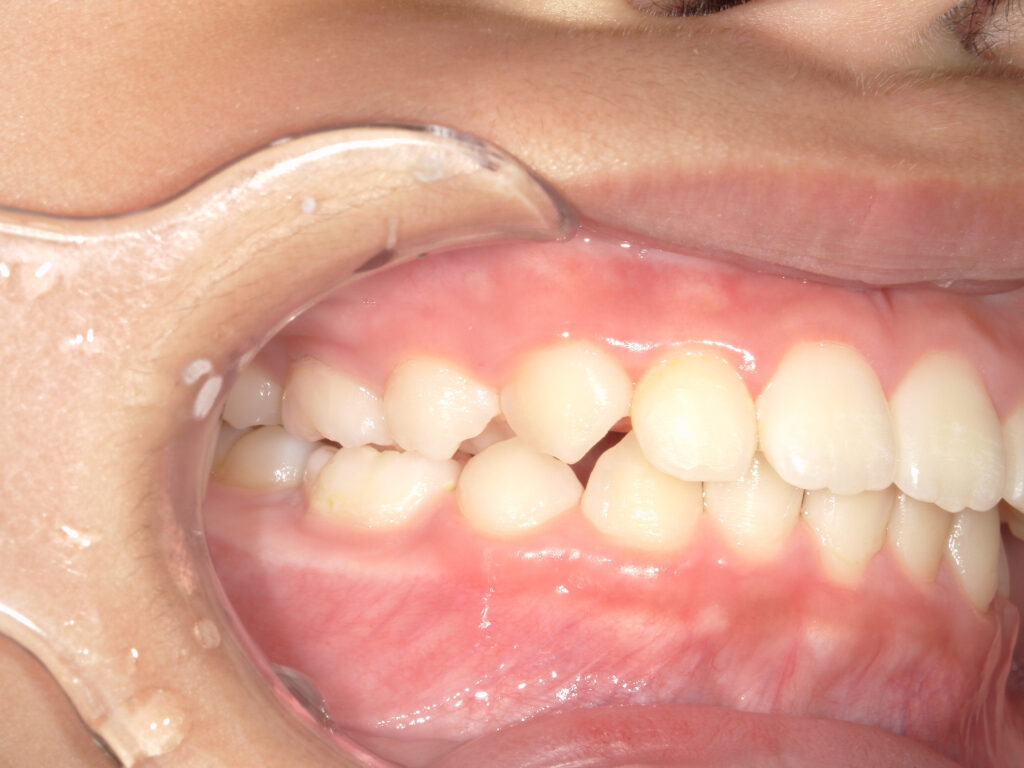

右側

治療前